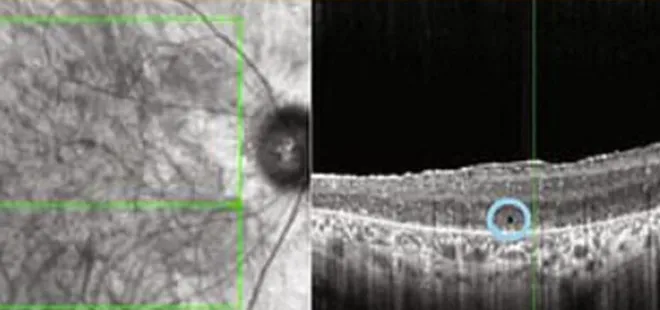

Aynı habere göre, terapi, hastanın gözlerinden birindeki hücreleri genetik olarak değiştirerek, özel bir gözlükle gönderilen ışık atımlarına tepki vermelerini sağladı.

Gözlüğün üzerindeki kamera ise gerçek dünyanın bir görüntüsünü, hastanın önündeki nesneleri tanıyabileceği kehribar renkli ışık darbelerine dönüştürdü.

Bu görüntünün siyah beyaz olduğunun altını çizen uzmanlar söz konusu yöntemin başka bir kişinin yüzünü tanımak için yeterince ayrıntılı olmadığını açıkladı.